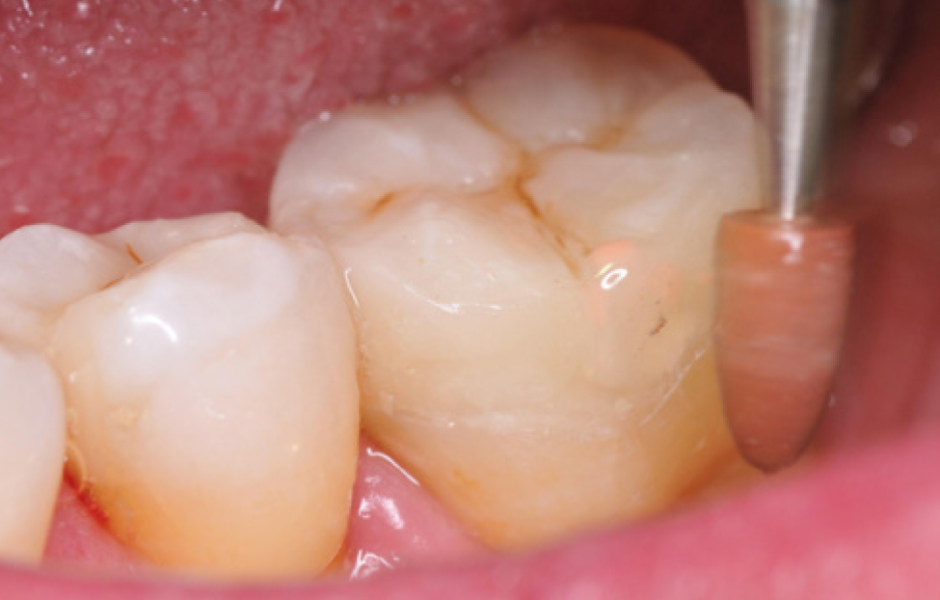

Obr. 4: Okamžité utěsnění dentinu. Obnažený dentin prvního moláru byl okamžitě ošetřen sealerem a byla provedena dostavba za použití SimpliShade Bulk Fill Flow (Kerr). Následně byly na premoláry umístěny dvě sekční matricové pásky pro postranní úsek, fixované oranžovým klínkem a kroužkem, pro zhotovení výplní II. třídy.

Obr. 5: Přímé výplně. Za dodržení zásad adhezivního postupu byly dokončeny přímé výplně na premolárech s použitím jednoho odstínu SimpliShade Bulk Fill (Kerr) a následně provedena individualizace okluze hnědými pigmenty. Díky snadné manipulaci a nízkému polymeračnímu smrštění bylo možné vyplnit obě kavity jedinou 4mm vrstvou kompozitu. Materiál byl přizpůsoben kavitě a modelován pomocí techniky Espresso posterior lines, což ušetřilo cenný čas.